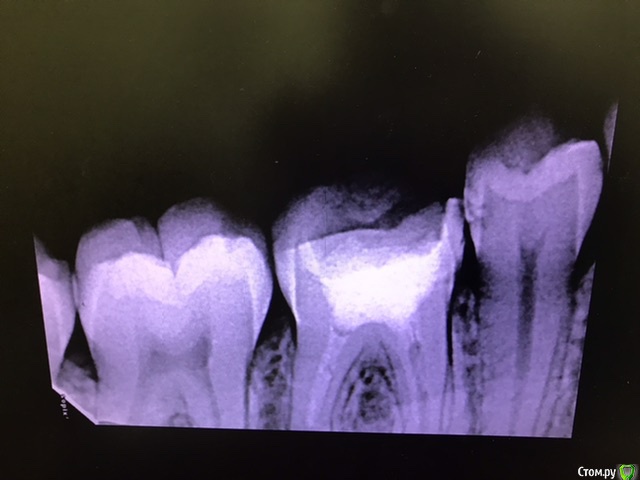

ho4u-vra4a Опубликовано 23 марта, 2020 Поделиться Опубликовано 23 марта, 2020 здравствуйте! обращаюсь к специалистам! пишу своим непрофессиональным языком, не судите строго.6 дней назад обратилась на перелечивание каналов с гранулемой ( или что это точно - я не знаю).46 зуб. мне установили коффердам, вскрыли старую пломбу, сверлили разными приборами, прочищали каналы, промывали хлоргексидином и гипохлоритом.весь процесс мучения длился полтора часа. в итоге мне запломбировали каналы с кальцием. поставили внутрь временную пломбу, а сверху еще закрыли постоянной. сделали рентген и отпустили домой. начинала я всю эту процедуру без анестезии, но в процессе все-таки попросила сделать её, так как было больно. и после того, как мне установили световую пломбу у меня уже начали боли в зубе усиливаться, а когда отошла заморозка - боли были невыносимые. врач сказала, что будет болеть, посоветовала пить ибупрофен.но я не ожидала, что боли будут настолько острые. к слову, мне не помогали ни ибупрофен, ни найз. я протерпела несколько дней, т.к врач не работала пару дней, и потом поехала к врачу снова. на мою просьбу сделать рентген - мне сказали, что я там все равно ничего не увижу. ок. они вскрыли мою световую пломбу, убрали все из зуба, включая пасту с кальцием, снова промыли все хлоргексидином, поставили туда внутрь так же хлоргексид и метронидазол. закрыли временной пломбой. боль во время данной процедуры прошла, но затем через несколько часов появилась снова. на следующий день я созвонилась с врачом, она сказала, что тогда придется пить антибиотики, т.к. уже началось воспаление и мой зуб "не прошел на герметичность". от предложенных антибиотиков я отказалась, т.к. у меня на них сильная аллергия. но указала, на какие группы антибиотиков у меня нет аллергии. врач сказала, что подумает и пригласила снова на осмотр на следующий день. в тот же день я открыла для себя кеторол, который помог заглушить острую боль. но появилось чувство распирания и как будто мне кололи в кость чем-то. на следующий день ( то есть уже сегодня) меня опять осмотрели, опять промыли каналы, опять поставили временную пломбу. через два часа я стала пить теплый ромашковый чай, и от него у меня снова острая боль. что мне делать? какие могут быть ошибки или может быть проблема в моем зубе и иммунитете? почему болит постоянно зуб, если причина боли должна уходить? прикрепляю рентген до и рентген после первого лечения. также есть КТ до перелечивания, вдруг кто-то заинтересуется. спасибо! 1 Ссылка на комментарий